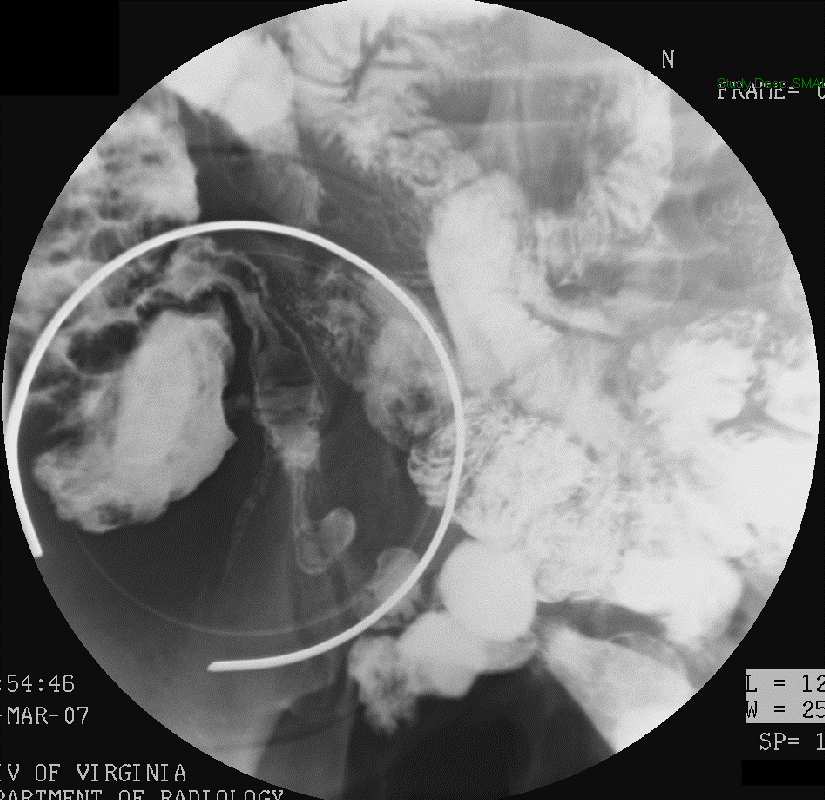

- When reviewing the preliminary scout film, you should see multiple surgical chain sutures in the pelvis

(key image 31)

(key image 32).